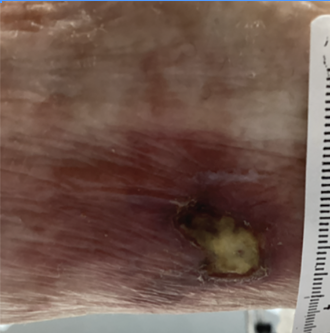

A 68-year-old female with a history of HTN, colon cancer in remission, stage 3 chronic kidney disease, cerebrovascular accident, and type 2 diabetes mellitus presented to a wound care center for evaluation of a painful wound on the posterolateral aspect of the left leg of 3 months’ duration for which she had completed multiple rounds of antibiotic treatment given by her primary care provider with no clinical improvement. The wound was well-demarcated, with a base of mixed fibrotic slough and small areas of necrosis. The surrounding skin demonstrated a dark, mottled erythema (Figure 1). On initial evaluation, the patient’s systolic pressure was 155 mm Hg and diastolic pressure was 79 mm Hg. She was initially diagnosed with a venous leg ulcer and returned for weekly light mechanical debridement because severe pain limited sharp debridement. The wound continued to increase in size over the next 6 weeks (Figure 2), leading to a more extensive workup to elucidate the etiology of this atypical presentation. Laboratory evaluation was unrevealing for underlying causes. Arterial studies revealed normal blood flow to the lower extremities. Biopsy of the site did not support vasculitis, immunobullous disease, or connective tissue disease, and there were nonspecific findings of epidermal necrosis and fibrin, and associated inflammation. Based on the clinical history, which included uncontrolled HTN, and the clinical presentation, a diagnosis of Martorell ulcer was made.

After the successful closure of the wound, the patient underwent a 28-day taper, and then pentoxifylline was discontinued. She remained ulcer-free for 5 months before presenting again with a very similar ulcer—this time on the contralateral leg (Figure 5). This posterolateral right leg ulceration was caught earlier than the ulcer on the left leg because the patient had already been established with the wound care team and her family had become vigilant participants in her hospice care. Anatomic location, near-identical contralateral wound appearance, and the patient’s persistently elevated blood pressure all suggested that this was a recurrence of Martorell ulcer. The patient was immediately restarted on pentoxifylline for treatment. Complete resolution of the Martorell ulcer was observed after only 29 days.